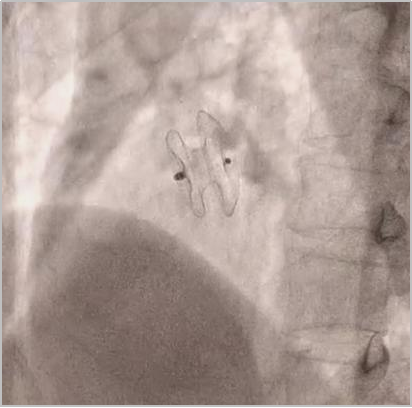

释放封堵器

释放封堵器后